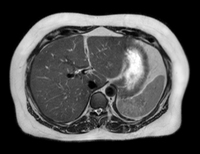

Magnetna rezonanca (eng. Magnetic Resonance Imaging), skraćeno MRI, je način snimanja Vašeg tijela bez korišćenja X zraka ili bilo kave radijacije. MRI aparat stvara slike koristeći magnetno polje koje se prirodno nalazi u našem organizmu. Magnetna rezonanca prikazuje meka tkiva tela (mišiće, nerve, mozak, pršljenske diskove, ligamente i td.). U mnogim situacijama magnetna rezonanca nudi jedinstvene informacije koje pomažu Vašem doktoru da odredi bolji plan terapije i nege.